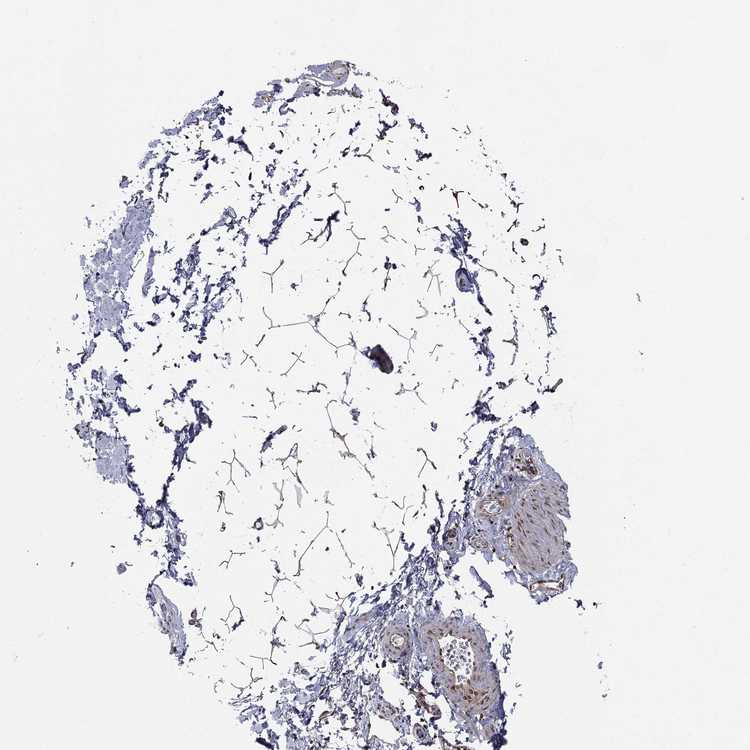

SOFT TISSUE 1 - Antibody stainingi

Antibody staining in the annotated cell types in the current human tissue is reported as not detected, low, medium, or high, based on conventional immunohistochemistry profiling in selected tissues. This score is based on the combination of the staining intensity and fraction of stained cells.

Each image is clickable and will lead to virtual microscopy that enables deeper exploration of all samples and also displays staining intensity scores, fraction scores and subcellular localization as well as patient and tissue information for each sample.

Antibody HPA049840Antibody HPA062236

Chondrocytes Not detectedNot detected

Fibroblasts Not detectedNot detected

Peripheral nerve Not detected-

SOFT TISSUE 2 - Antibody stainingi

Chondrocytes -Not detected

Peripheral nerve -Medium